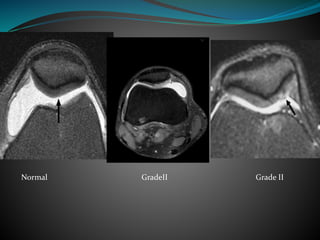

Chondromalacia patella

 Inflammation of underside of patella and

softening of cartilage.

 Common in young adults, can mimic meniscal

tear

Grade MRI finding

I Focal signal intensity changes without contour deformity

(difficult to assess on MRI)

II Focal signal intensity change and contour bulge (partial

thickness)

III Focal signal intensity change, contour irregularities, cartilage

thinning and fluid extension into cartilage (full thickness)

IV Similar to stage III with defects extending to the cortical bone

(with subchondral bony changes)

Normal GradeII Grade II